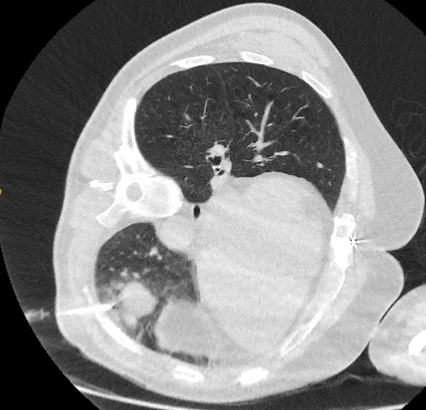

Computed tomography (CT) sections from two cases with benign perifissural nodules. Note the smooth margins and the normal undisturbed adjacent fissure

From the collection of Dr George Tsaknis, MD, PhD, FRCP(London), MRQA, MAcadMEd, PGCert; used with permission